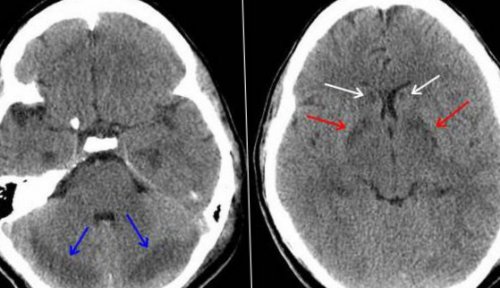

Диагностика отравления угарным газом

Диагностика